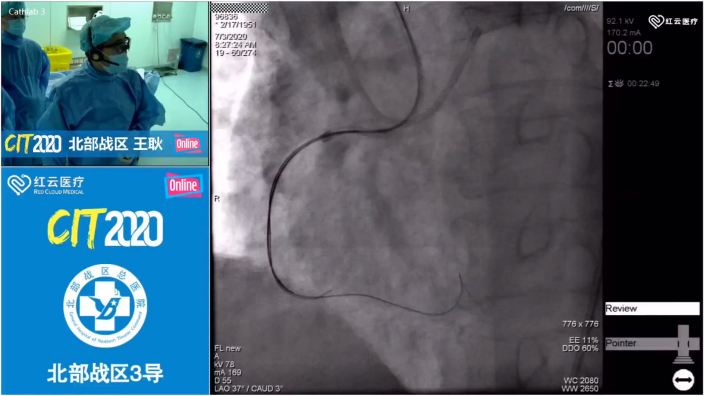

7月3日,备受期待的CIT2020 Online第二期手术转播活动正式开始。

北部战区总医院作为多次参加CIT手术转播的团队,本次共完成了4例手术演示,分别是王耿教授带来的复杂PCI、徐凯教授的TAVR、荆全民教授、刘海伟教授带来的CTO-PCI。

王耿教授进行演示的患者处于慢性闭塞病变和心梗血栓之间,采用血栓抽吸后效果良好。王耿教授在术中边操作边进行讲解:“复杂PCI在疏通血管的同时,不能给病人心功能造成进一步的打击,术中要特别注意不能再丢失血管。”